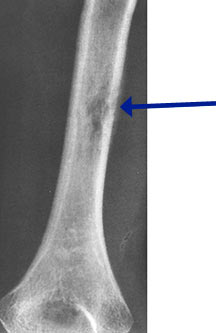

- May arise from any bone and any site within a bone (epiphyseal, metaphyseal, diaphyseal)

- Radiographically variable appearance: may appear benign (geographic) or malignant (permeative or moth eaten)

- Femur

- Humerus